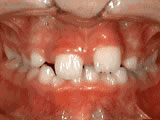

Overjet (Protruding Teeth)

Patient began treatment at age 10 for a severe overjet; two treatment phases guided jaw growth and aligned teeth. By age 13, she had a balanced, confident smile.

Overjet - Protruding front teeth after